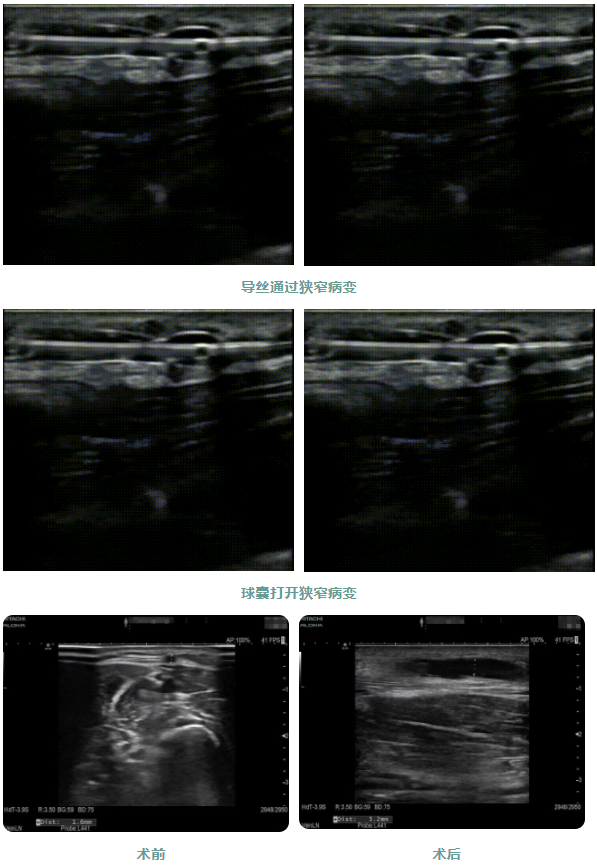

患者1年前出現(xiàn)周身乏力伴有雙下肢水腫癥狀,在外院行“為腎透析的動(dòng)靜脈造瘺術(shù)”后規(guī)律透析治療。因內(nèi)瘺無震顫2日,為求系統(tǒng)治療來院,入院后腎內(nèi)科金明花主任帶領(lǐng)醫(yī)護(hù)團(tuán)隊(duì)立即完善相關(guān)檢查,診斷為:動(dòng)靜脈內(nèi)瘺血栓形成,經(jīng)超聲檢查發(fā)現(xiàn)動(dòng)靜脈內(nèi)瘺血栓形成狹窄,最窄處內(nèi)徑約1.6mm。

為了節(jié)約患者有限的血管資源,盡早治療,經(jīng)過腎病內(nèi)科金明花主任及科室共同討論并爭(zhēng)得患者家屬同意后,決定對(duì)患者進(jìn)行超聲引導(dǎo)下動(dòng)靜脈內(nèi)瘺球囊擴(kuò)張術(shù)+血栓碎栓術(shù)解決內(nèi)瘺狹窄及血栓。手術(shù)過程中金明花主任在內(nèi)瘺狹窄位置近心端進(jìn)行穿刺,沿穿刺針置入導(dǎo)絲、置入血管鞘,在超聲實(shí)時(shí)引導(dǎo)下球囊到達(dá)病變部位,緩慢擴(kuò)張球囊,解決狹窄病變,并壓碎血栓,使內(nèi)瘺通暢。整個(gè)手術(shù)僅用30分鐘,用時(shí)少,效果明顯,術(shù)后內(nèi)瘺血管雜音及震顫明顯,手術(shù)效果立竿見影。